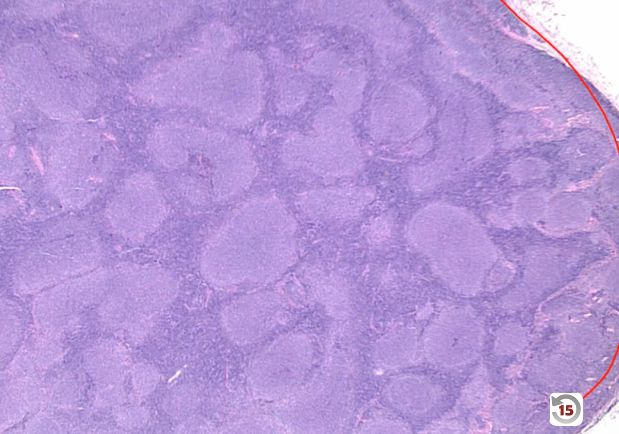

What form of non-Hodgkin lymphoma is seen in the image below? _____